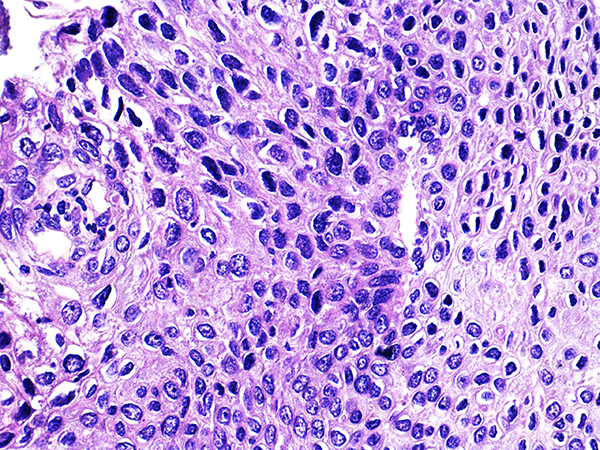

Case 4

Soft Bx CIN 3

40x - High Power |